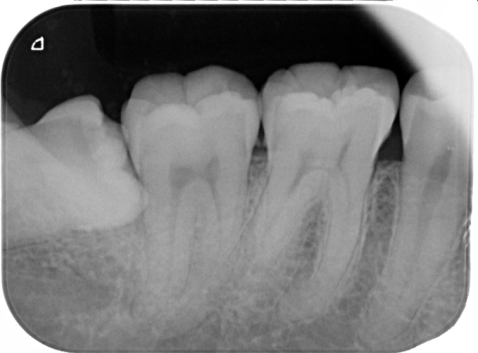

3.上顎と下顎の噛み合わせる歯がどちらかにない時は歯がだんだん伸びてきて、顎の運動を邪魔してしまい、関節が痛くなることがあります

きっちりした良いかみ合わせですが、一部奥に親知らずがあります。上顎にかみ合う歯が無いので、だんだん上へ伸びています。

下顎を前の方へ動かしたとき、伸びている親知らずは上の歯とぶつかってしまいます。こんな時、スムーズな顎の運動が出来なくなり、関節が痛くなります。